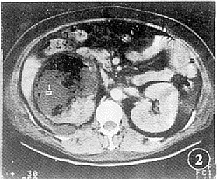

平扫示右侧肾影明显增大变形,肾实质密度不均匀,示大片状低密度积液影及点、片状更低密度积气影,可见液平,CT值分别为17 HU、-1000 HU(图1);肾脏边缘毛糙,肾筋膜增厚,肾周脂肪间隙模糊,示液体密度影填充。左肾大小、形态未见明显异常。增强检查,右肾门平面上内侧肾实质轻度强化,所扫低密度影无强化(图2)。

图1 CT平扫示右肾区有一12 cm×12 cm类圆形包块影,后内侧为肾影,周围为混杂密度影,其中有气体。左肾大小、形态无明显异常